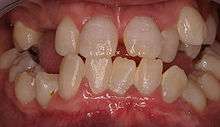

Dentin dysplasia is a genetic disorder of teeth, commonly exhibiting an autosomal dominant inheritance. It is characterized by presence of normal enamel but atypical dentin with abnormal pulpal morphology. There are two types. Type I is the radicular type, and type II is the coronal type. In the radicular type, the roots of teeth are shorter than normal and the pulp chamber may be nearly gone. The pulp chamber is sometimes described as having a "crescent shaped" appearance. In the coronal type, the pulps are enlarged and are described as having a "thistle tube" appearance, in permanent dentition. In the deciduous dentition, coronal dentin dysplasia bears a resemblance to Dentinogenesis Imperfecta type II.

Type 1: Roots are short, blunt and conical. In deciduous teeth, pulp chambers and root canals are completely obliterated while in permanent they may be crescent shaped.

Type 2: The pulp chamber of the deciduous teeth become completely obliterated. The permanent teeth displays large pulp chamber in the coronal portion of the tooth - referred to as thistle tube appearance. Pulp stones may be found.